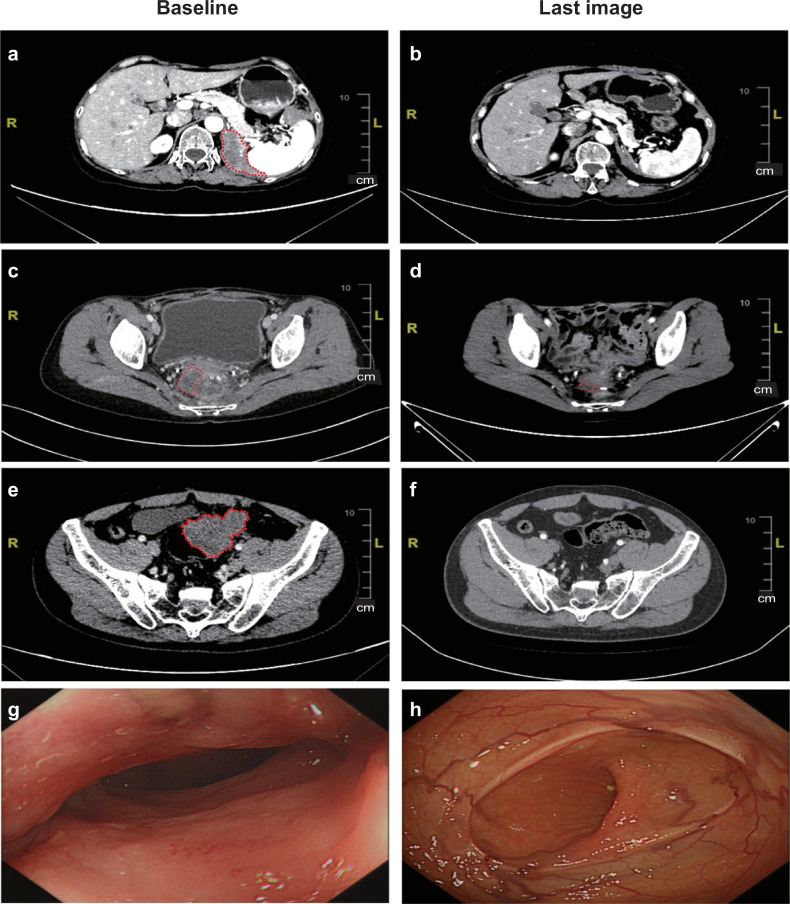

Figure 1a–c present the overall results stratified by TMB, cancer type, and POL functional mutation/hypermutation.17 The median overall survival was 17.9 months, with a 95% confidence interval of 13.5 to not reached (NR), as shown in Fig. 1d. The median progression-free survival was 2.5 months, with a 95% confidence interval of 1.4 to NR, as shown in Fig. 1e. Figure 2 illustrates the baseline and post-treatment examinations of three patients with objective tumor responses. Patient SYSUCC07, diagnosed with R682Q POLD1 germline mutant renal medullary carcinoma, achieved partial response after two doses of toripalimab. Despite discontinuing treatment after seven cycles due to grade three treatment-related pneumonitis, the patient continued to exhibit a persisting partial response with a progression-free survival of 39.9 months (Fig. 2a, b). Patient SYSUCC09, who had local recurrent colon cancer with S297F and S1906Y POLE mutations and had previously received two lines of palliative systemic treatment, also achieved a partial response after 18 doses of toripalimab. She has completed 2-year treatments with a persisting partial response at the last follow-up (Fig. 2c, d). One patient (SYSUCC10) achieved a complete response after receiving protocol treatment. This 45-year-old male had local recurrent colon cancer and liver metastasis with P286R and F1907L POLE mutations. After standard palliative chemotherapy, he was enrolled in this clinical trial. He achieved a partial response after receiving 14 doses of toripalimab and a complete response after 26 cycles of treatment, with both coloscopy and PET/CT scan confirming no tumor residue. At the last follow-up, he had completed two-year treatments and achieved a confirmed complete response (Fig. 2e–h).

Fig. 2.

Objective tumor responses in three patients with metastatic solid tumor. CT scan showing peritoneal metastasis and its evolution between baseline (a) and after toripalimab (b) of patient SYSUCC07 with metastatic renal medullary carcinoma harboring R682Q germline POLD1 mutation. c, d The regression of the peritoneal metastasis of patient SYSUCC09 diagnosed with colon cancer harboring S297F and S1906Y POLE mutation. e, f The locally recurrent primary tumor and its evolution between pretreatment and after toripalimab in patient SYSUCC10 diagnosed with colon cancer harboring P286R and F1907L POLE mutation, who achieved complete response. g, h The colonoscopy image at baseline and after treatment of patient SYSUCC10, respectively